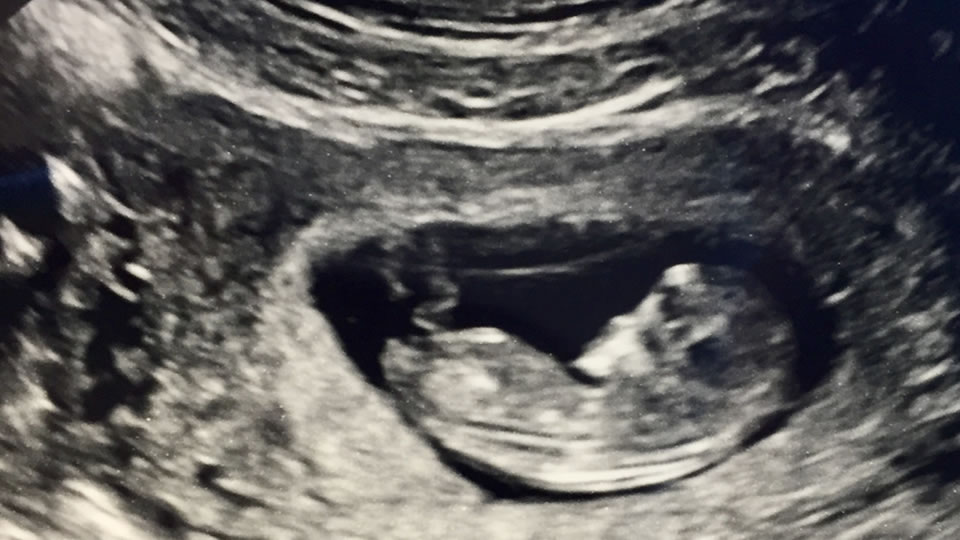

A few days ago, I sat in my car after a doctor’s appointment and marveled at what we had just experienced. Using a wand and a computer, the sonogram technician measured our baby’s bones and the circumference of her skull. She measured our baby’s heart rate and blood flow through the umbilical cord. She took pictures of our baby’s nose, lips, feet and hands. We watched the baby practice breathing. At the end, a doctor took this data and told us what we needed to do to keep her as healthy and happy as possible.